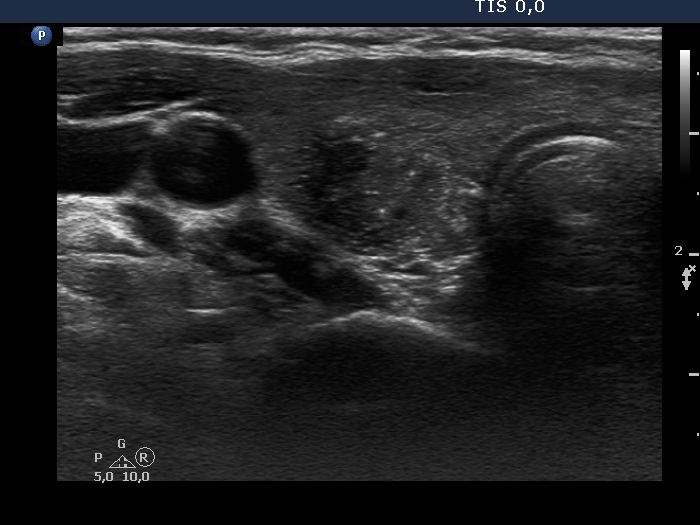

Intrathyroidal parathyroid adenoma (histological diagnosis) - case 1399 |

Papillary carcinoma (histological diagnosis) - case conp 031 |

There are a few hyperechogenic granules within the small parathyroid lesion and we can see two much thinner lines, as well. These figures might be either punctate echogenic foci or non-specific granules. The papillary carcinoma contains punctate echogenic foci. The main differences between the appearance of the cases are the shape and borders: regular and sharp in the left benign, while irregular, blurred in the right malignant focus.